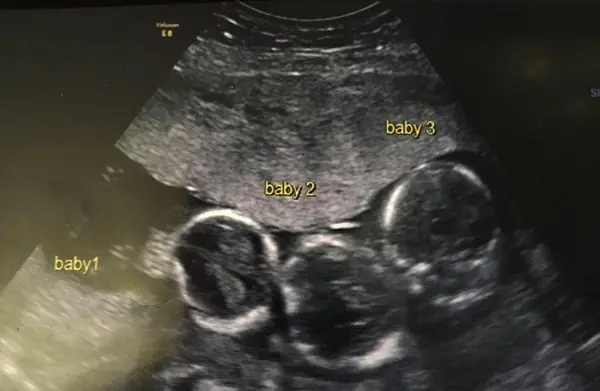

The family, from Liverpool, England, had always dreamed of having more children and growing their family. But nothing could have prepared them for what the ultrasound revealed. They weren’t just expecting one baby… or even two. They were expecting triplets—and not just any triplets, but identical ones.

During her pregnancy, Becki began suffering from intense headaches. Concerned, her doctors performed an ultrasound to ensure everything was alright.

“It was the biggest shock of my life,” Becki told the Liverpool Echo. “We haven’t got any triplets in the family, so it came completely out of the blue.”